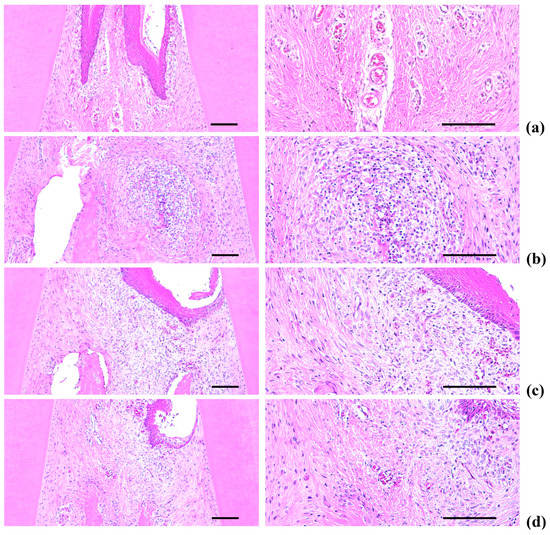

2.5. Histopathology of the Maxillary Regions

Marked increases in inflammatory cell infiltration (mainly polymorphneutrophils (PMNs)) were found in the gingival tissues between the upper left and right incisors in the EPD control, including severe edematous changes; i.e., loosening of the collagen fibers and a loss of compactness. We also observed increased activation of osteoclast cells, as well as increases in the number and percentage of regions occupied by osteoclasts on the alveolar bone surface (OS/BS) in the alveolar bone areas of the EPD control, accompanied by a marked decrease in the volume of osteoid alveolar bone. It follows that periodontitis and related alveolar bone loss was induced by the ligature placements. However, the histopathological evidence for periodontitis, as well as the infiltration of inflammatory cell, the loosening of collagen fiber, the activation of osteoclast cells, and the decrement of the volume of osteoid alveolar bone, was markedly reduced by oral treatment with IND, as well as by topical application of Polycal at all three concentrations compared with the EPD control rats (Table 2, Figure 9 and Figure 10).

Figure 9.

Representative histological images of gingival tissues between upper incisor teeth, taken from Intact or EPD rats around upper left incisor teeth: (a) Intact control (Normal control, non-ligated and distilled water topically applied rats); (b) EPD control (Ligated EPD induced and distilled water topically applied rats); (c) IND (Ligated EPD induced and indomethacin 5 mg/kg orally administered rats); (d) Polycal-H (Ligated EPD induced and Polycal 50 mg/mL solution topically applied rats); (e) Polycal-M (Ligated EPD induced and Polycal 25 mg/mL solution topically applied rats); and (f) Polycal-L (Ligated EPD induced and Polycal 12.5 mg/mL solution topically applied rats). All H & E stain. Scale bars = 120 µm.

2.5.1. Changes on the Numbers of Inflammatory Cells Infiltrated in Gingival Tissues

Significant (p < 0.01) decreases of the numbers of inflammatory cells infiltrated in gingival tissues were detected in all test substance treated rats including IND 5 mg/kg oral administered rats as compared with EPD control, respectively. Especially, all three different concentrations of Polycal topical applied rats showed decreases of gingival inflammatory cells around ligation placed as compared with EPD control rats (Table 2, Figure 9).

2.5.2. Changes on the Collagen Fiber Occupied Regions in Gingival Tissues

Significant (p < 0.01) increases of collagen fiber occupied regions in gingival tissues were detected in all test substance administered rats including Polycal 50 mg/mL concentration topically applied rats as compared with EPD control, respectively. Especially, all three different concentrations of Polycal topical applied rats showed increases of collagen fiber occupied regions in gingival tissues around ligation placed as compared with EPD control rats (Table 2, Figure 9).

As with previous EPD studies [42,43], periodontitis leads to marked infiltration of inflammatory cells, as well as edematous changes in the gingival tissues between the upper incisors. In addition, we found evidence of absorption of the alveolar bones due to osteoclast cell activity via histopathological observations. Increases in histological scores are associated with infiltration of inflammatory cells and alveolar bone damage [4,23,44]. The infiltration of inflammatory cells, decreases in collagen-occupied regions related to edematous changes, decreases in bone volume, increases in the number of osteoclast cells and increases in the ratio OS/BS that were detected via our histomorphometrical analyses are consistent with previous reports [7,8]. These histopathological changes related to periodontitis and alveolar bone loss were reduced markedly with oral administration of IND, as well as by topical application of Polycal at all three concentrations, in which the response was concentration response trend.